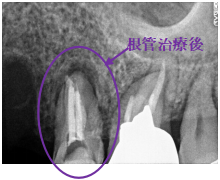

水平に破折していました。破折していた部分を取り除き、根管治療をし、ファイバーコアをいれ、オールセラミック冠を被せました。

所感

今まで、他の歯を治療した時は、すべてメタルフリーの治療をされていて、オールセラミック冠の良さを実感されていましたので、今回もオールセラミックを選択されました。

オールセラミック冠(失活歯):¥104,500(税込)

Before

破折した部分を取り除いたところ

After

根管治療後